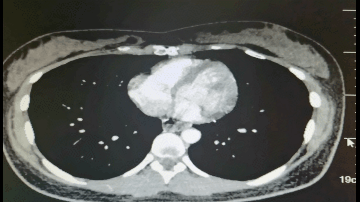

◈ 2022年8月26日,患者突发腹部疼痛。急诊行腹部CT检查提示:盆腔见较大不规则形混杂密度影,与双侧附件及邻近肠管、右侧髂血管分界不清,最大层面约13.4cm×11.8cm,其内密度不均,可见片状高密度影及钙化密度影,病变周围似见稍高密度包膜影。左上腹部小肠旁见肿块影,与局部肠管分界不清,局部肠管走行紊乱,管壁似欠连续,腹腔内见较多液体密度影及游离气体密度影。网膜略增厚。

2022年8月26日 腹部CT

◈ 检查结论:1、盆腔占位病变,对比2022-07-15片似变大,建议进一步检查。2、腹腔游离气体、考虑消化道穿孔,左上腹部小肠旁占位性病变,3、腹腔积液,对比前片积液量减少,网膜略增厚。